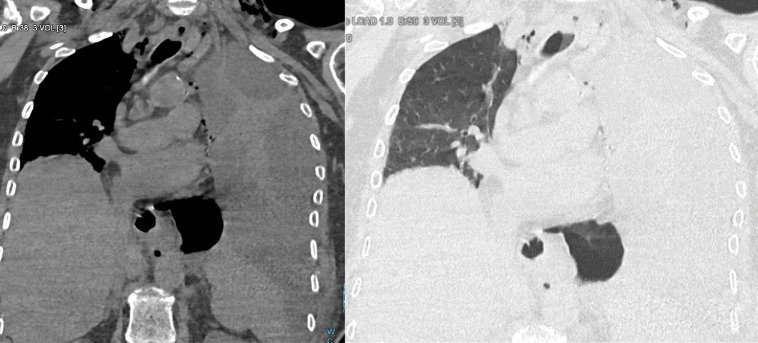

本文报告一位70岁女性患者,长期以进食困难伴固体食物为主诉,报告Boerhaave综合征。她腹痛24小时,伴有恶心和粪便性呕吐。患者有呼吸急促、心动过速、缺氧、腹部守卫、无肠音。胸腹计算机断层扫描显示幽门壁明显增厚,伴有继发性胃膨胀、颈部皮下肺气肿、双侧胸腔积液和纵隔气肿。

A case is presented of Boerhaave syndrome in a 70‑year‑old female patient complaining of dysphagia with solids for a long time. She consulted for abdominal pain for 24 hours, accompanied by nausea and fecal vomiting. The patient had tachypnea, tachycardia, hypoxia, abdominal guarding, and absence of bowel sounds. Thoracoabdominal computed tomography revealed significant pyloric wall thickening with secondary gastric distension, cervical subcutaneous emphysema, bilateral pleural effusion, and pneumomediastinum.